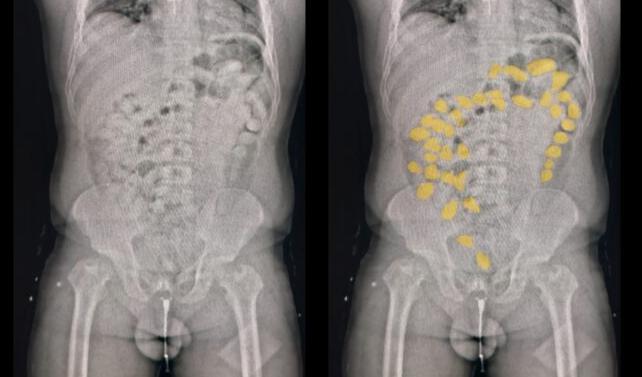

Fuentes del caso indicaron que médicos asistían anoche a los dos bolivianos sobre la base de un protocolo de evacuación. Primero, les habrían realizado ecografías y otros estudios, a fin de contabilizar las cápsulas con cocaína. Al cierre de edición, las "mulas" habían expulsado 187 cápsulas y seguía el procedimiento.

Tomando como base el estado individual de los "pacientes", los médicos resolvían el método de evacuación. El resto, solo será paciencia y tediosa espera para los gendarmes. Luego, los espera el Federal para indagarlos.